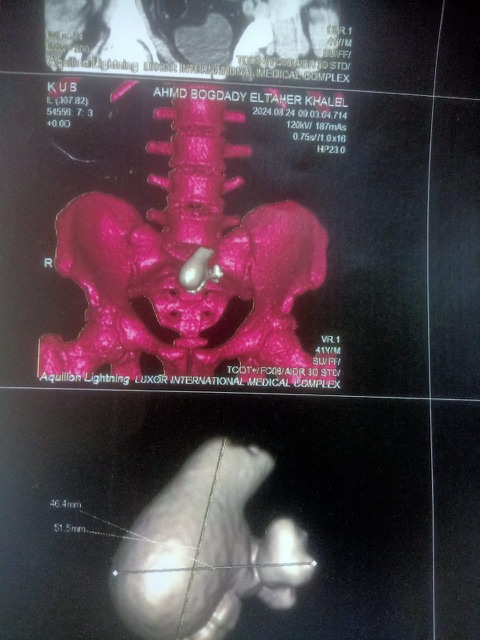

واستقبل مجمع الأقصر الطبي الدولي المريض أحمد بغدادي الطاهر، 43 عاما، مصاب بآلام حادة ونزيف دموي في الجانب الأيمن من المعدة ناحية الكلى، وعقب الفحوصات تبين وجود عدد من الحصاوى، أكبر واحدة تزن كيلوم جرام في واقعة فريدة من نوعها.

ونجح أطباء قسم المسالك البولية بالمجمع الطبي الدولي، برئاسة الدكتور باسم نبيل رئيس القسم، الدكتور إيهاب جمال والدكتور حافظ بدوي والدكتور حسن عكاشة، في إتمام عملية جراحية خطيرة لانتشال الحصول التي كادت تتسبب في إيقاف عمل الكلى مما يستوجب إخضاعه إلى الغسيل الكلوي، وذلك بمساعدة الدكتور عصام أحمد والدكتورة جهاد أحمد علي، أطباء التدخير وعدد من طاقم التمريض.